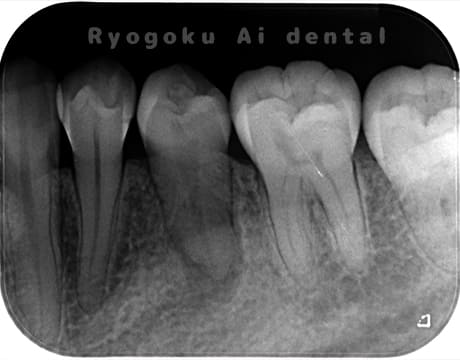

Case23

- 原因

- 慢性根尖性歯周炎

- 治療内容

- マイクロエンド

- 治療費用

- 121,000円

他院で抜歯を診断され、セカンドオピニオンで来院された患者様です。根管治療を行い、サイナストラクト(フィステル)が消失しました。今後、被せ物の治療を行なっていきます。